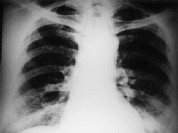

单项选择题女,34岁, 新月体肾炎患者,最近咳嗽咯血, 第一次行胸片检查考虑为双下肺感染,抗感染治疗后无明显好转, 症状加重,4天后复查并行CT检查如图, 应考虑为 ( )